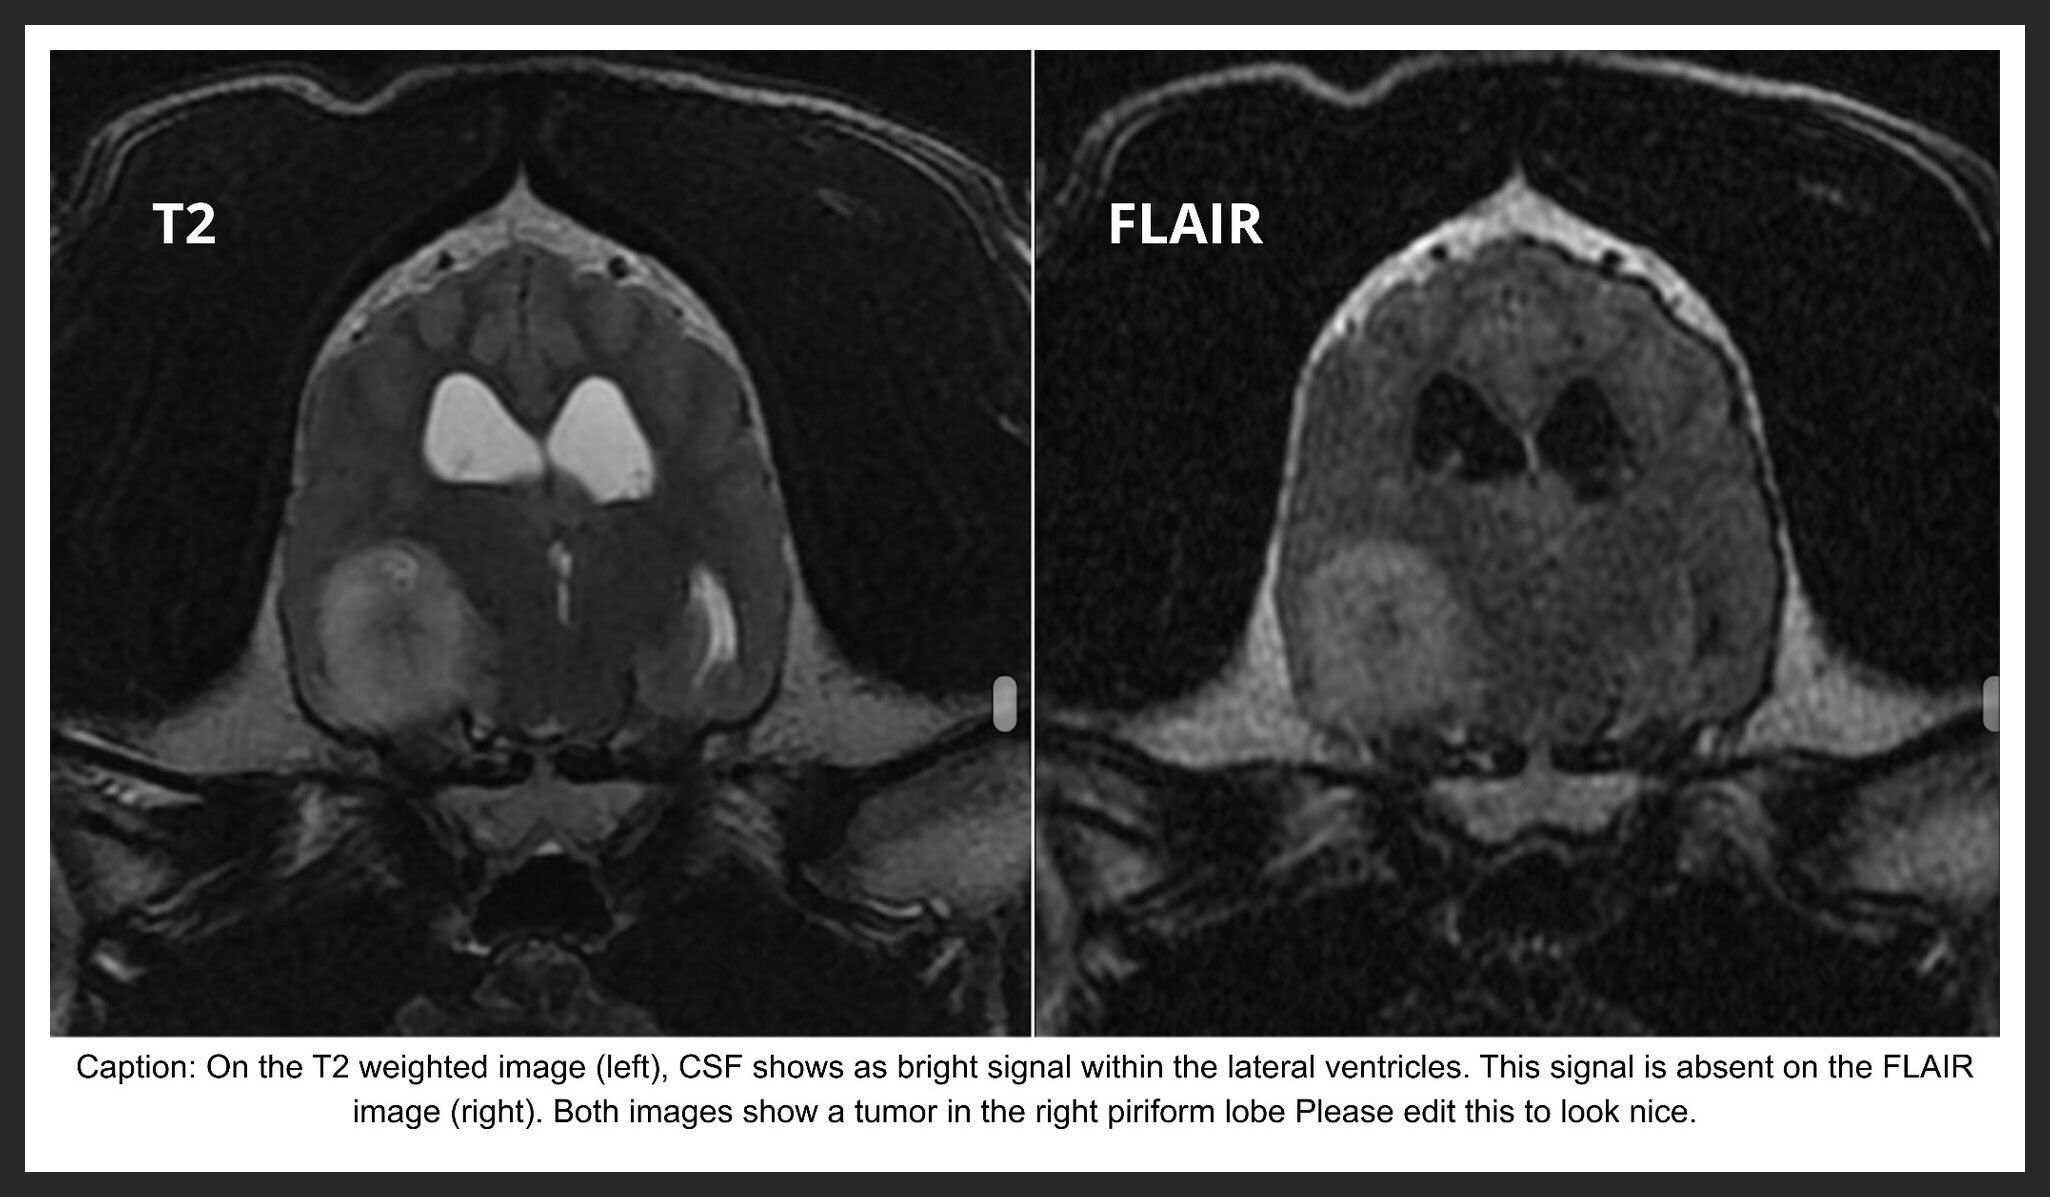

RF pulses are applied in various imaging “sequences,” each designed to highlight specific physical or chemical tissue characteristics. These sequences are interpreted together to build a comprehensive diagnostic picture. For example, a FLAIR (fluid-attenuated inversion recovery) sequence suppress signal from free fluid and is routinely used in neuroimaging to eliminate cerebrospinal fluid signal, improving evaluation of periventricular brain tissue and highlighting edema. Other sequences suppress fat signal (e.g., STIR, SPAIR, spectral fat saturation) to accentuate inflammation or fluid accumulation. Additional specialized sequences can also detect hemorrhage. As with CT, contrast agents may be administered to further characterize inflammation, vascularity, or neoplasia.